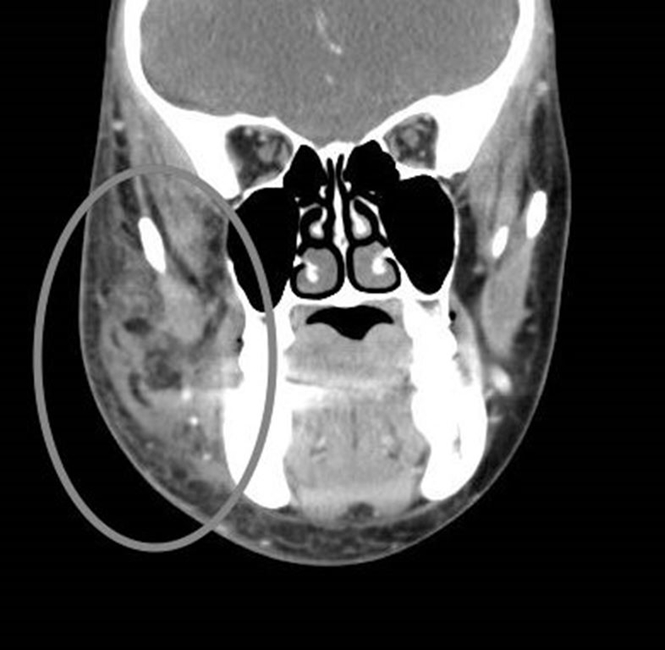

W trybie ostrego dyżuru wykonano badanie tomografii komputerowej twarzoczaszki ze wzmocnieniem kontrastowym oraz podstawowe badania laboratoryjne. W badaniach laboratoryjnych nie stwierdzono podwyższonych markerów charakterystycznych dla infekcji. Badanie tomografii komputerowej uwidoczniło naciek tkanek miękkich policzka prawego od zęba 12 do 17. Nie stwierdzono masywnych cech rozpadu tkanek ani kolekcji płynowych pochodzących z chemicznego rozpadu i upłynnienia uszkodzonych tkanek. Występowały liczne pęcherzyki powietrza w tkankach miękkich prawej strony twarzy, klinicznie wywołujące objaw krepitacji (crepitatio) (ryc. 2a, 2b, 2c).

Ryc. 2a. Wybrany przekrój czołowy tomografii komputerowej ze wzmocnieniem kontrastowym. Zaznaczono zmienione tkanki miękkie.

Ryc. 2b. Wybrany przekrój czołowy tomografii komputerowej ze wzmocnieniem kontrastowym. Zaznaczono zmienione tkanki miękkie.